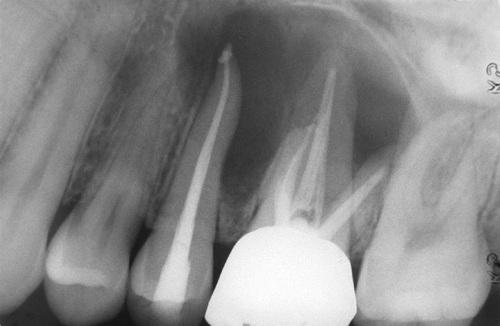

Radiolucent lesion located lateral to the roots of a vital mandibular canine and first premolar.

lateral periodontal cyst

A larger lesion located lateral to the roots of two vital teeth, causing root divergence.